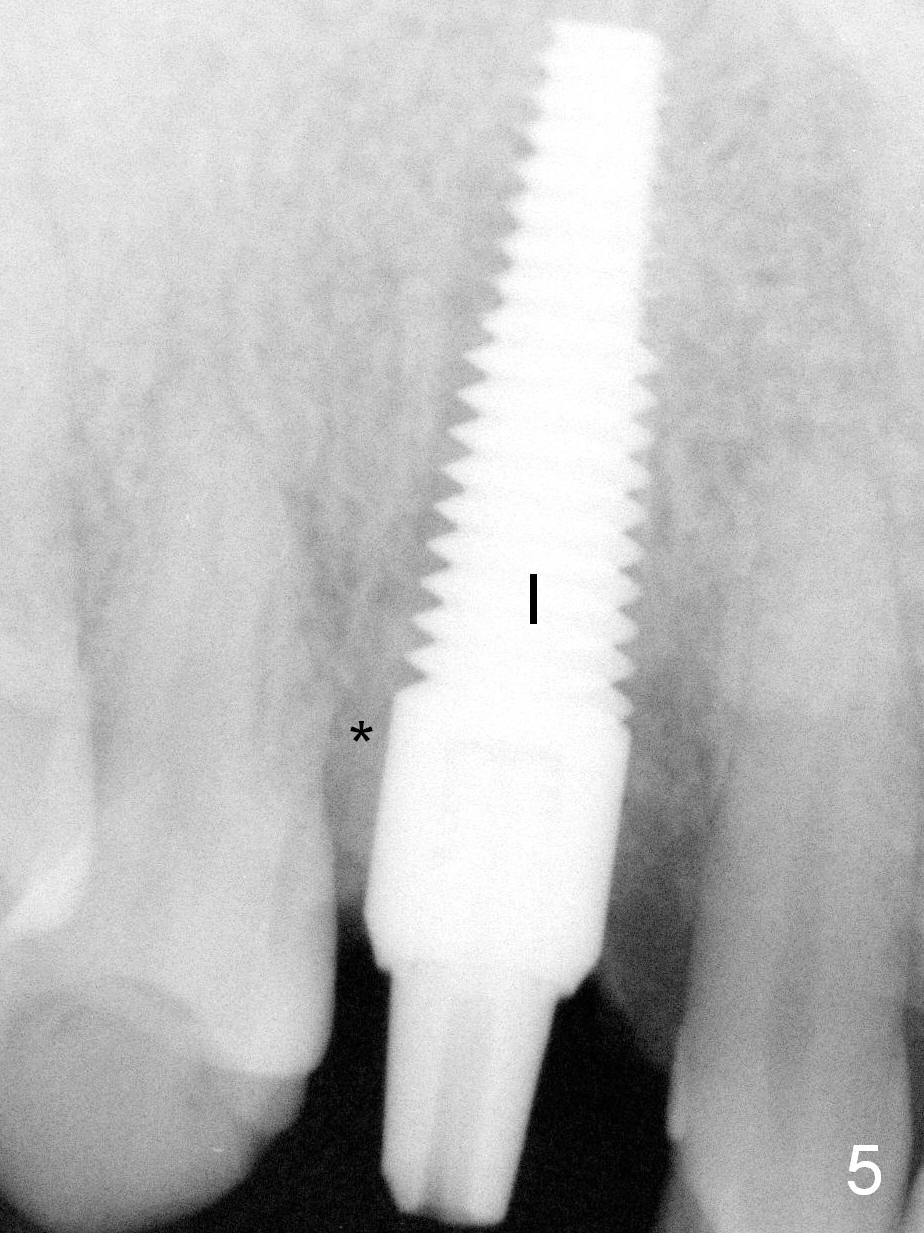

After a 5x20 mm implant (Fig.5 I) is placed, the distal gap is filled with bone graft (*).